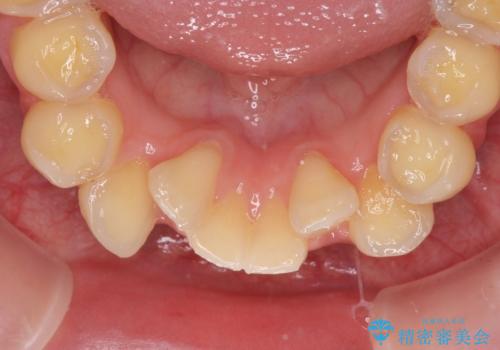

- 一時期の拒食症に伴い歯が酸で溶けてボロボロになってしまったとのことで来院された患者様です。

酸によりエナメル質の大半が溶けており、下顎前歯以外は酷いむし歯のような状態でした。

当初はほとんどの歯をむし歯治療のようにオールセラミッククラウンにて補綴治療を行う予定でしたが、仮歯に置き換えた時点で、口元の突出感や下顎前歯の叢生が気になるとのことで、上下左右の第一小臼歯4本を抜歯したワイヤー装置での抜歯矯正を行うこととしました。